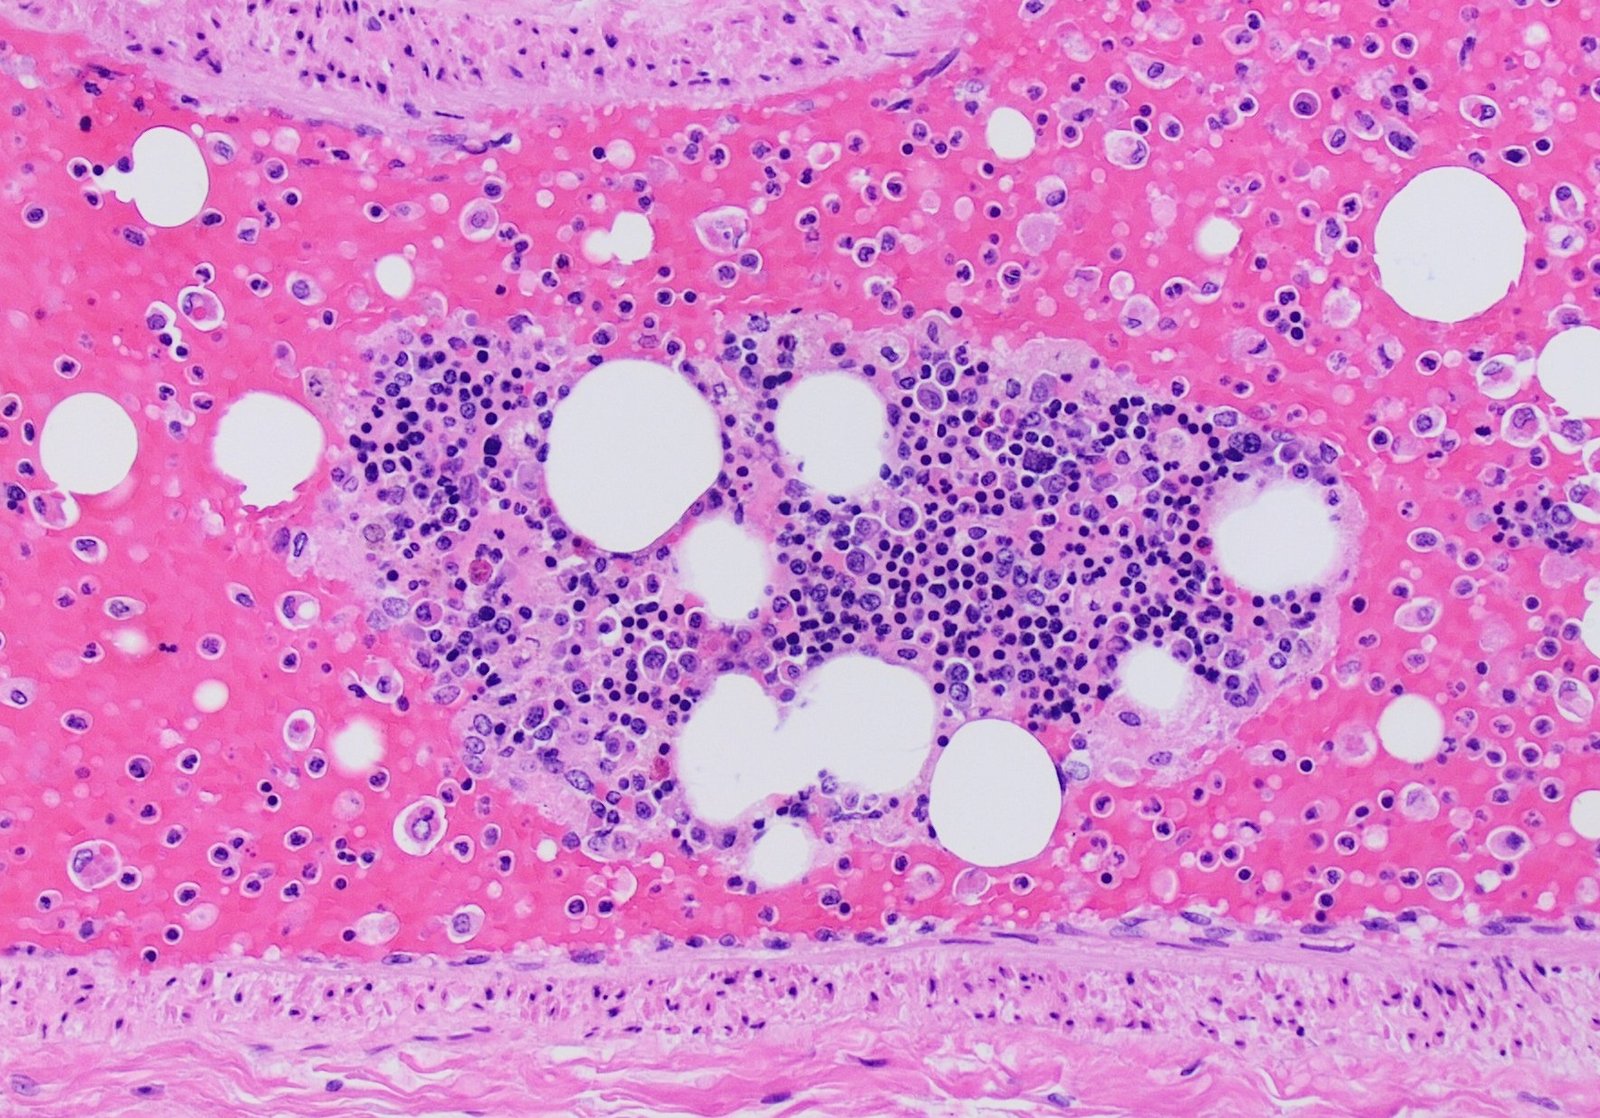

Fat embolism occurs when fat is released into blood from bone marrow, becomes entrapped in the lung capillaries and occluded the small vessels that supply brain, kidney and other organs.

1. Minute and micro- haemorrhage in the lung capillaries.